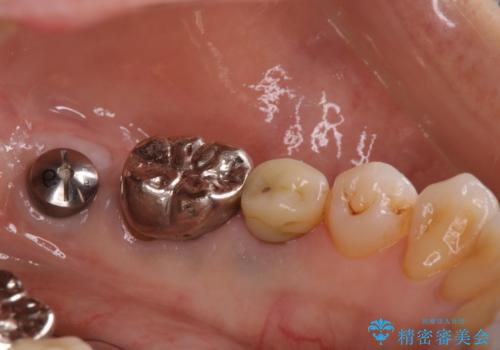

- 食事の度に、歯の中に物がつまるとのことで来院された患者様です。

精密検査を行った結果、歯が折れていたため保存は難しく、インプラント治療になりました。

現在は、違和感なども無くなり、固いものも食べられると喜ばれていました。

インプラント治療をすることによってしっかりと噛めるようになりました。